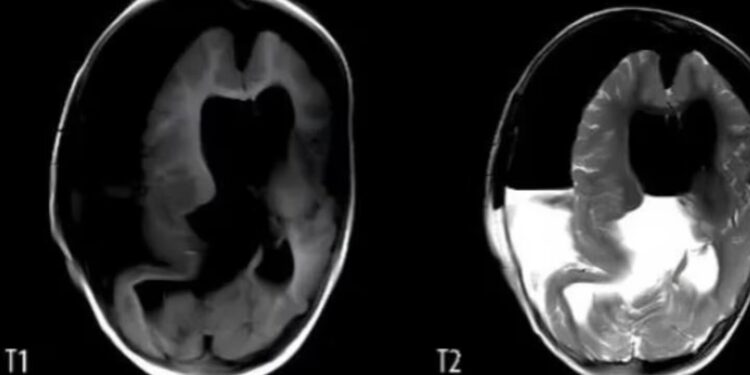

En el caso de esta beba, los médicos detectaron anomalías en su cráneo a las 33 semanas de gestación, durante un examen prenatal. Pero, la resonancia magnética no pudo proporcionar más información. La beba nació por cesárea a la semana 37 y los médicos notaron que su cabeza era notablemente más grande que lo normal.

Al ingresar al hospital, al año de vida, su tamaño era anormal. Además, según detallaron los médicos que la atendieron, la nena solo podía decir “mamá” y apenas movía la cabeza. No podía sentarse ni gatear.

Tras de la craneotomía que le realizaron, los médicos indicaron: “Extrajimos un embrión inmaduro, con vérnix y órganos visibles, como la boca, los ojos, la cabeza fetal, el pelo fetal, el cuerpo, el antebrazo, las manos y los pies”. A su vez, detallaron que el embrión medía 18 cm de largo, tenía rasgos y extremidades malformadas, así como huesos largos y una columna vertebral.